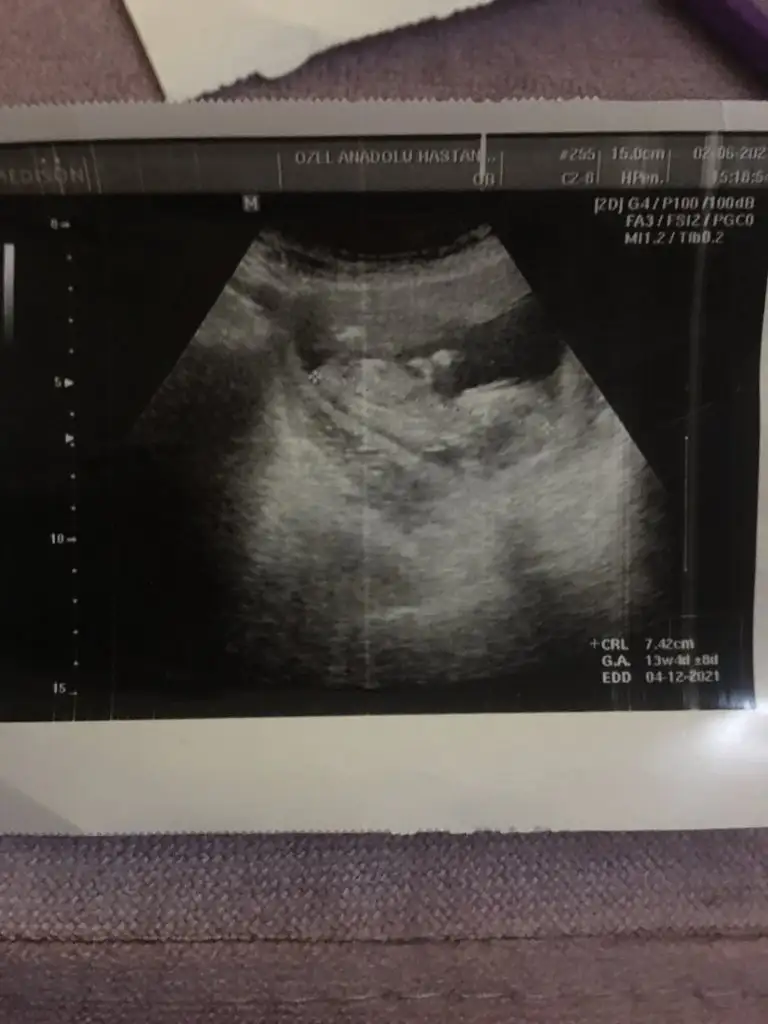

Bende yeniyim öncelikle☺️Mesajlarınızı dikkatle okudum bana da doktorum kesin birşey demedi 13.haftadayım yorumlar Mısınız acaba

25,9 KB · Görüntüleme: 92